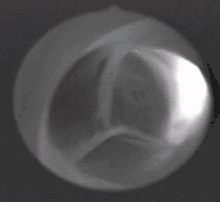

يتكون الصمام من ثلاث شُرَف (باللاتينية: Valvulae) تلتقي معاً على شكل نجمة ثلاثية، تحوي هذه الشرف على مخارج الشرايين التاجية.

شُرَف الصمام على شكل جيوب تخرج من حلقة دائرية من النسيج الضام، تلتقي أطرافها الحرة في المنتصف لتشكل حين انغلاقها شكل نجمة ثلاثية (تشبه نجمة المرسيدس)، وتكون أطرافها سميكة لتضمن الانغلاق المتكامل. شُرَف الصمام الأبهري هي:

يتشكل الصمام الأبهري والصمام الرئوي ما بين الأسبوع الخامس إلى الأسبوع السابع للتخلق المضغي.[2] كنوع من التنوع الخِلقي يمكن أن ينشأ الصمام الأبهري بشرفتين، وفي حالات نادرة جداً بشرفة واحدة. الصمامات بشرفتين تتعرض لاحتكاك أشد على أطرافها من تلك التي تأتي بثلاث شُرَف، مما يعرضها بنسبة أكبر للتكلّس وبالتالي للتضيّق.[3]

![]() مقطع عرضي للصمام الأبهري، يُظهر الشرف الثلاث منغلقة، كما يُظهر مخرج الشريان التاجي الأيسر فقط. |